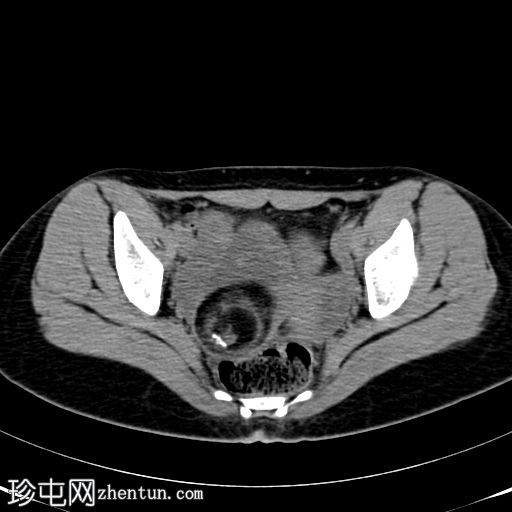

CT扫描

轴向扫描

非造影扫描

盆腔内可见巨大脂肪密度肿块,伴有牙齿。